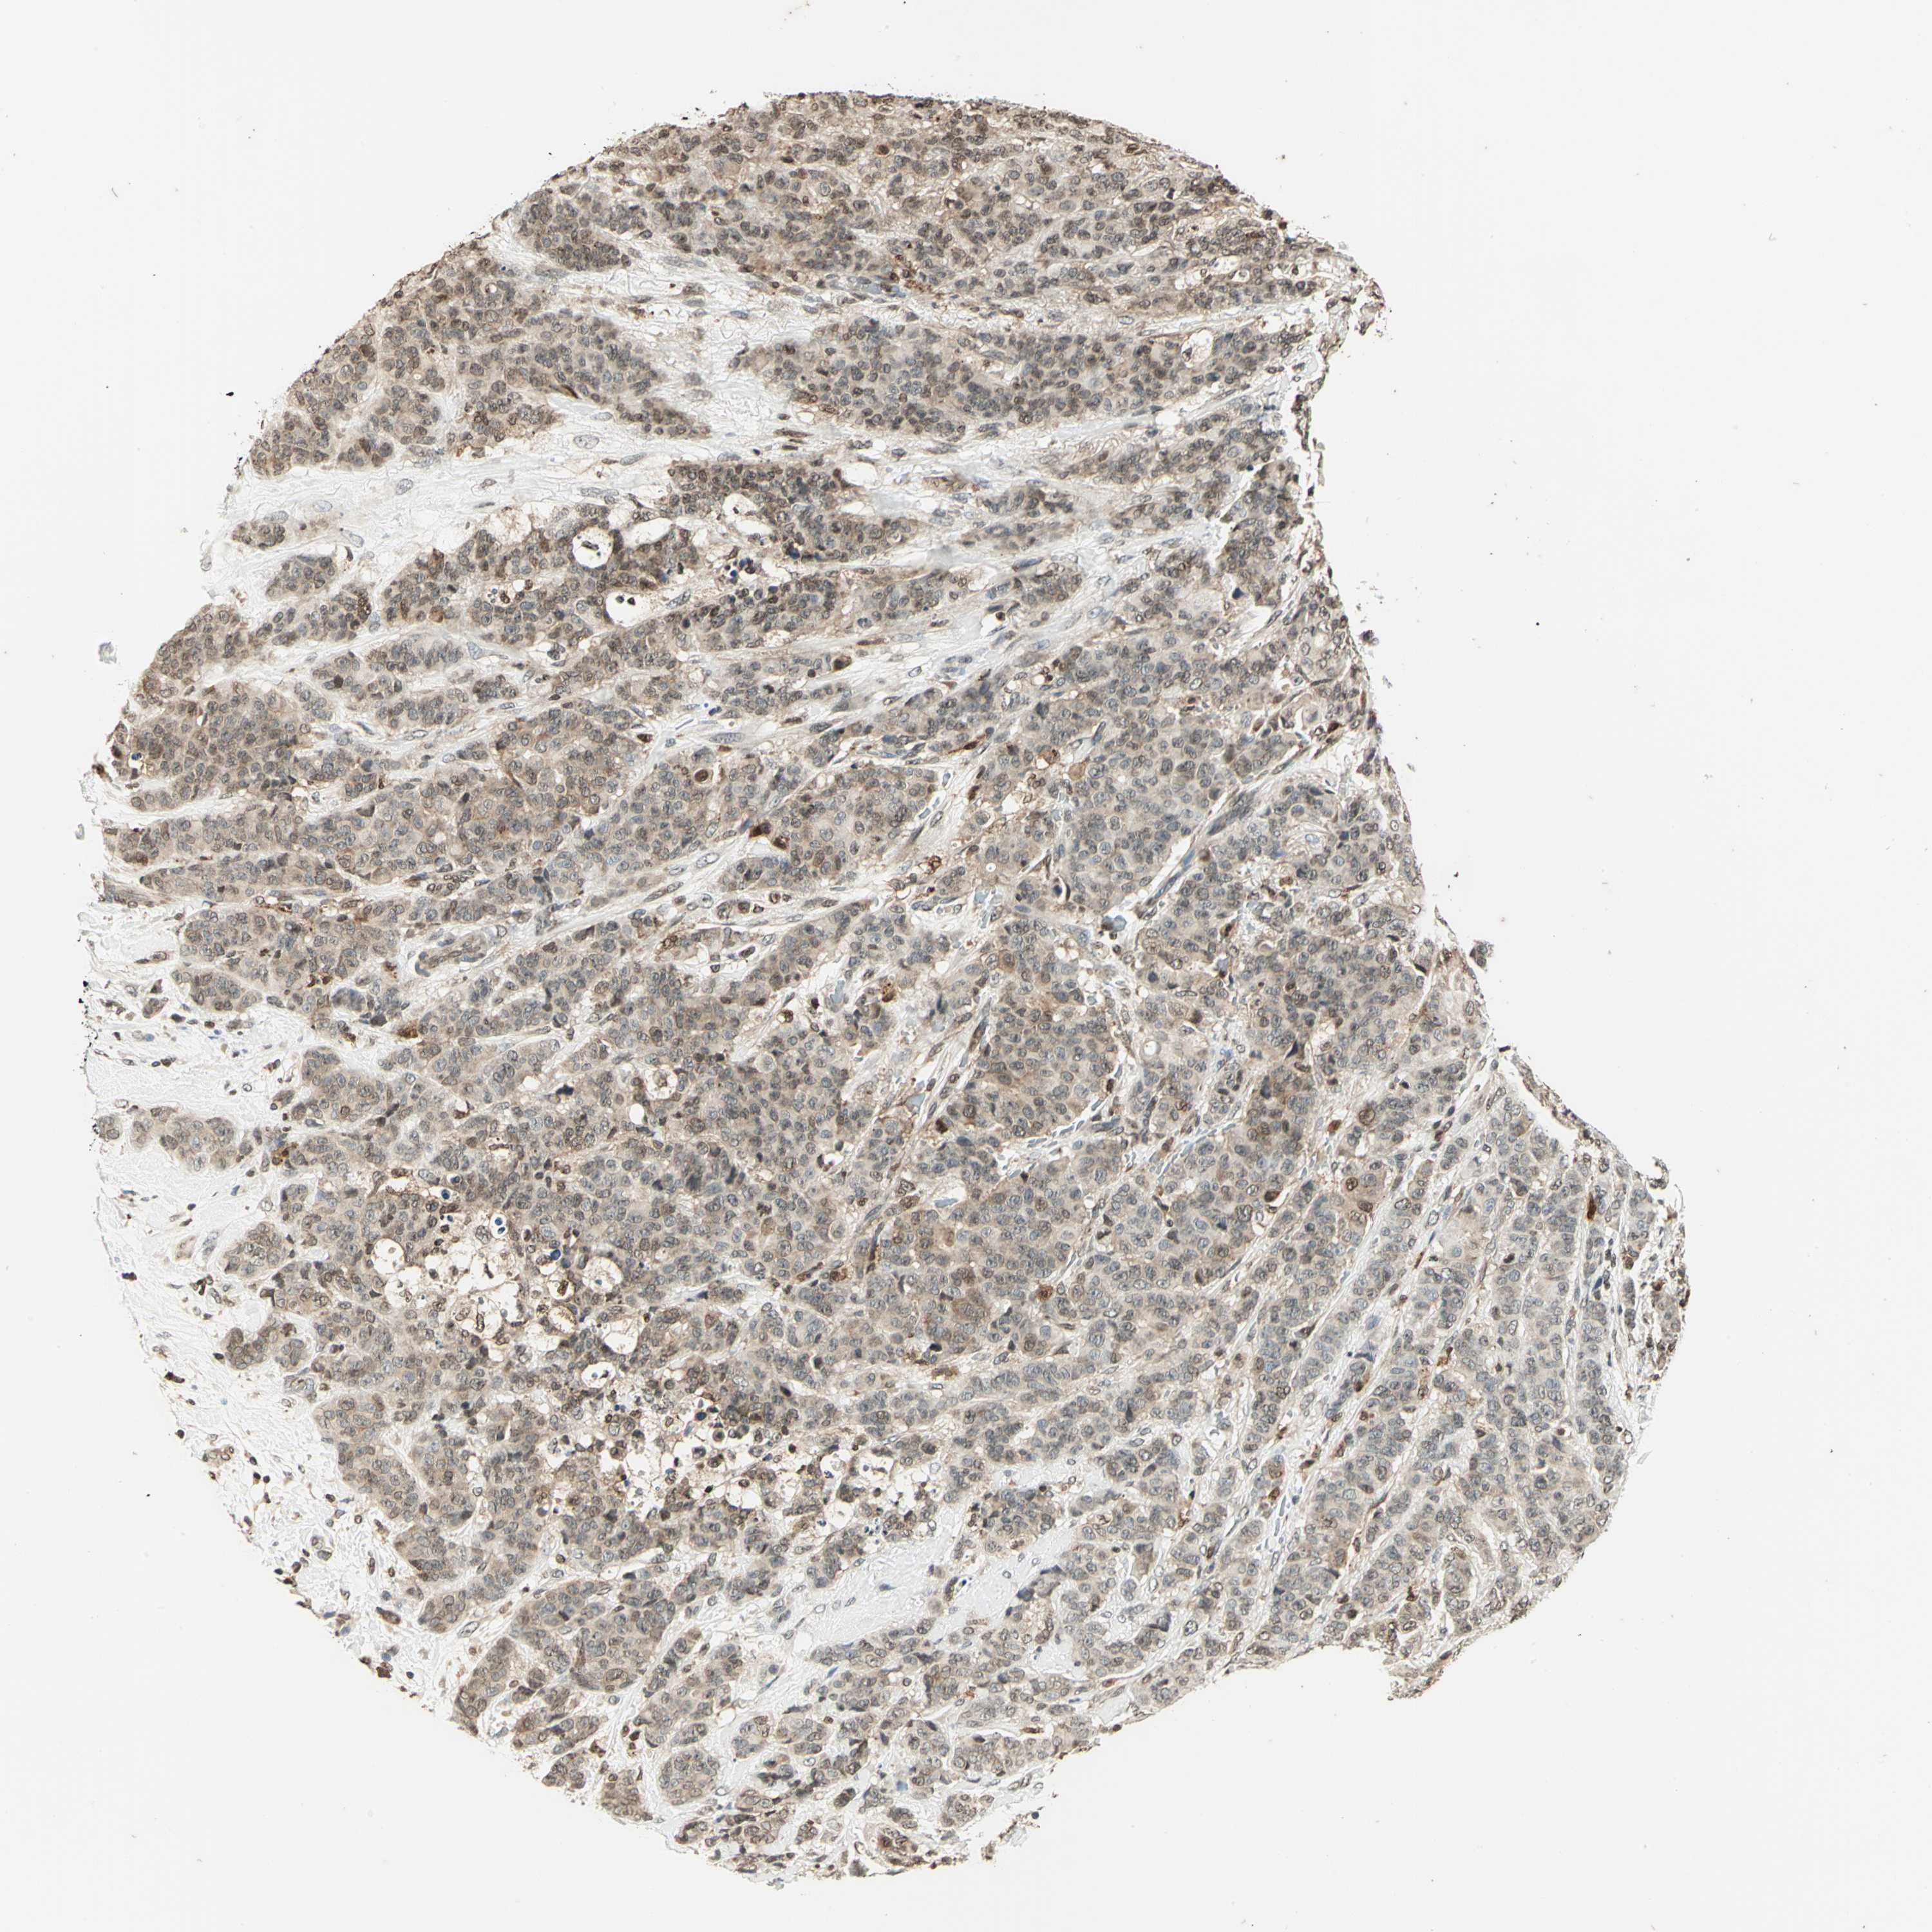

CANCER BREAST CANCER Show tissue menu

BRCA TCGA BRCA VALIDATION PROTEIN EXPRESSION

ANTIBODIES

AND

VALIDATION